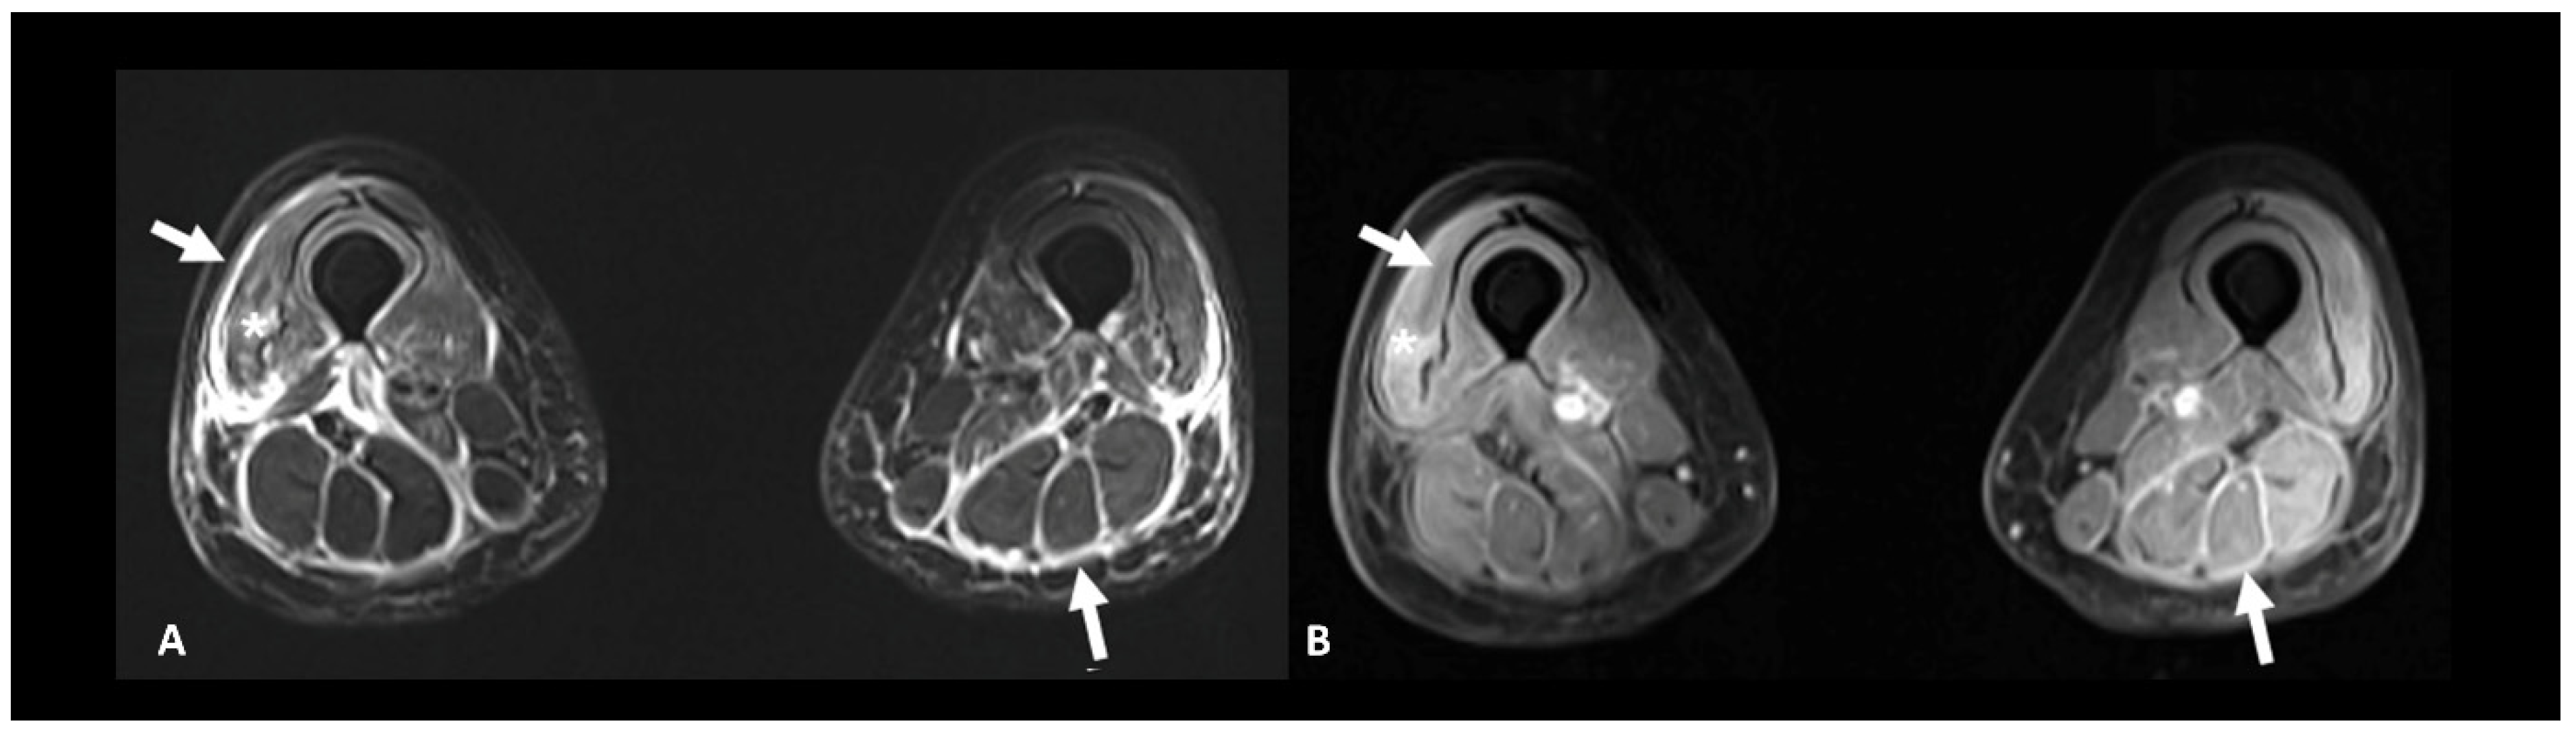

2.6. Ir-Rheumatological and Musculoskeletal Adverse Events

- Ponce, A.; Frade-Sosa, B.; Sarmiento-Monroy, J.C.; Sapena, N.; Ramírez, J.; Azuaga, A.B.; Morlà, R.; Ruiz-Esquide, V.; Cañete, J.D.; Sanmartí, R.; et al. Imaging Findings in Patients with Immune Checkpoint Inhibitor-Induced Arthritis. Diagnostics 2022, 12, 1961. [Google Scholar] [CrossRef]

| Myopathy | Serum-specific antibodies, screening for concurrent myocarditis, EMG +/− muscle biopsy | Other causes of myopathy | Muscular T2 hyperintensities | |